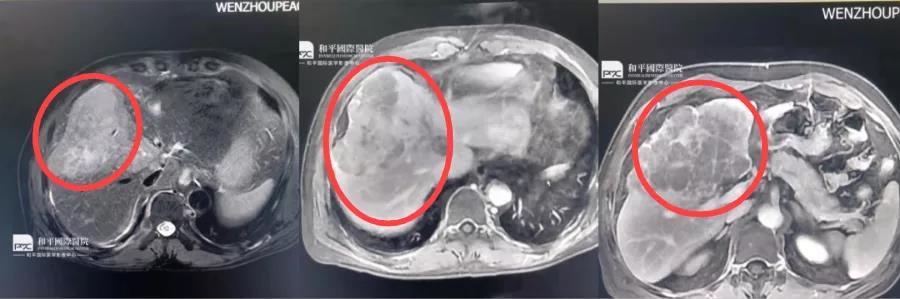

換家醫(yī)院檢查,結(jié)果卻是天壤之別,真相是......

換家醫(yī)院檢查,結(jié)果卻是天壤之別,真相是......古人云差之毫厘,謬以千里在醫(yī)學(xué)影像的世界里有時(shí)正是那毫厘的差距竟是癌與非癌的差別甚...

第一次做磁共振檢查就......

第一次做磁共振檢查就......關(guān)于癌癥,大家都避之不及。很多被檢查出肝癌的患者,通常都無(wú)法接受這個(gè)事實(shí),我明明就...